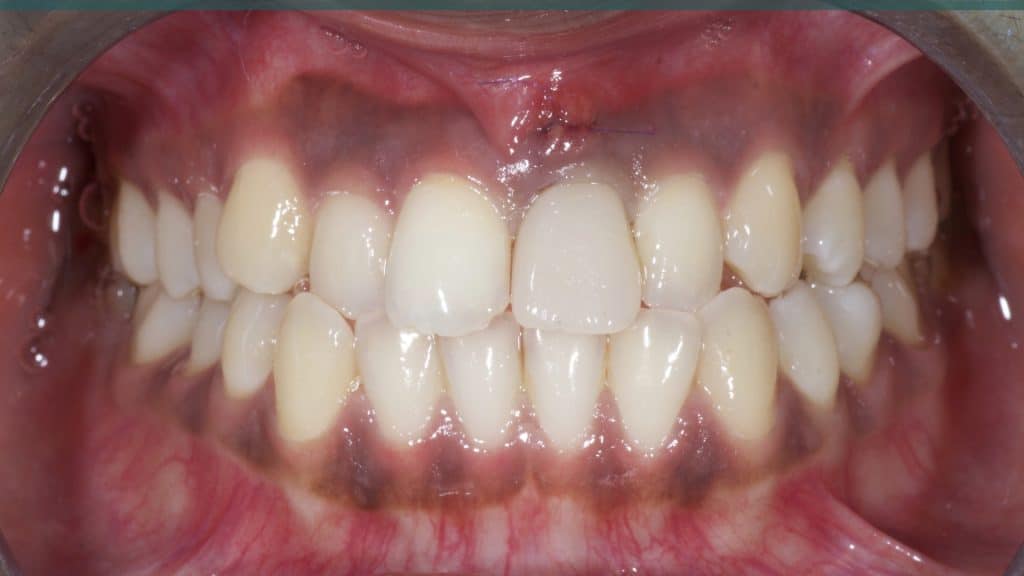

A 27-year female patient with dislodged Resin bonded FPD. She had that FPD for past few years, it had metal wings on palatal surfaces of UR1 and UL2 and a post like metal extension into the root canal of UL1. There was gingival abscess due to fractured root segment most probably due to extended metallic post like structure. Immediate implant placement (IIP) and Immediate restoration (IR) was planned for this patient.